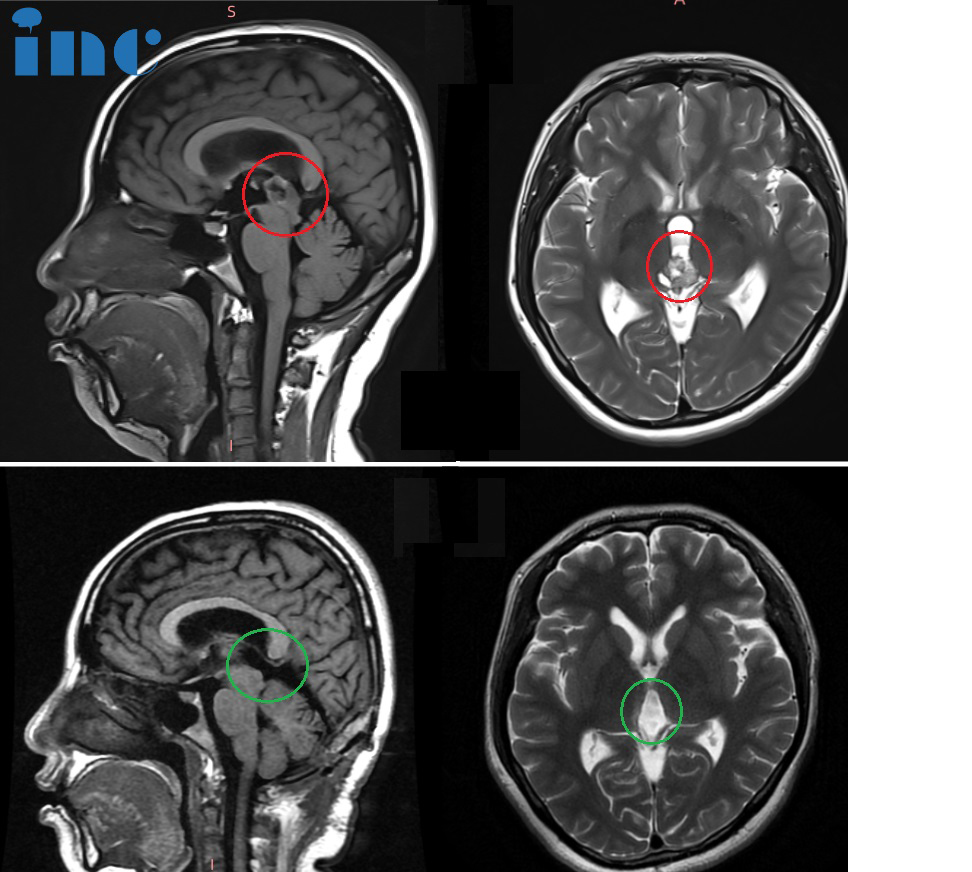

CASE 4:40岁女士-松果体肿瘤

术前(红色):在松果体区域显示出对比度增强的团块,并向下延伸到四脑室。脑干出现水肿。

术后(蓝色):松果体肿瘤被完整切除,无严重神经功能损伤(术后影像为术中磁共振检查时的瘤腔填充物)

病史摘要:40多岁秦女士,头晕、双眼复视,被发现有“松果体及四脑室占位”,4年间辗转治疗,症状仍无缓解,出现肢体无力等。经历了数次伽马刀及立体定向放射外科治疗,症状反而加重,又出现了走路不稳、视力下降、脑积水等其他更多症状。行“松果体区肿瘤切除术”,但只有小部分肿瘤得到切除,术后症状未见明显好转,并逐渐恶化加重。

手术入路:使用小脑幕上、幕下联合入路来到达肿瘤区域实现全切除

术后情况:术后2天即拔除气管,自主呼吸正常,身体体征正常,迁出ICU,复视好转。术后5天在陪同下床康复锻炼,头晕明显好转,肌力好转。术后18天顺利出院,无新发神经功能缺损。